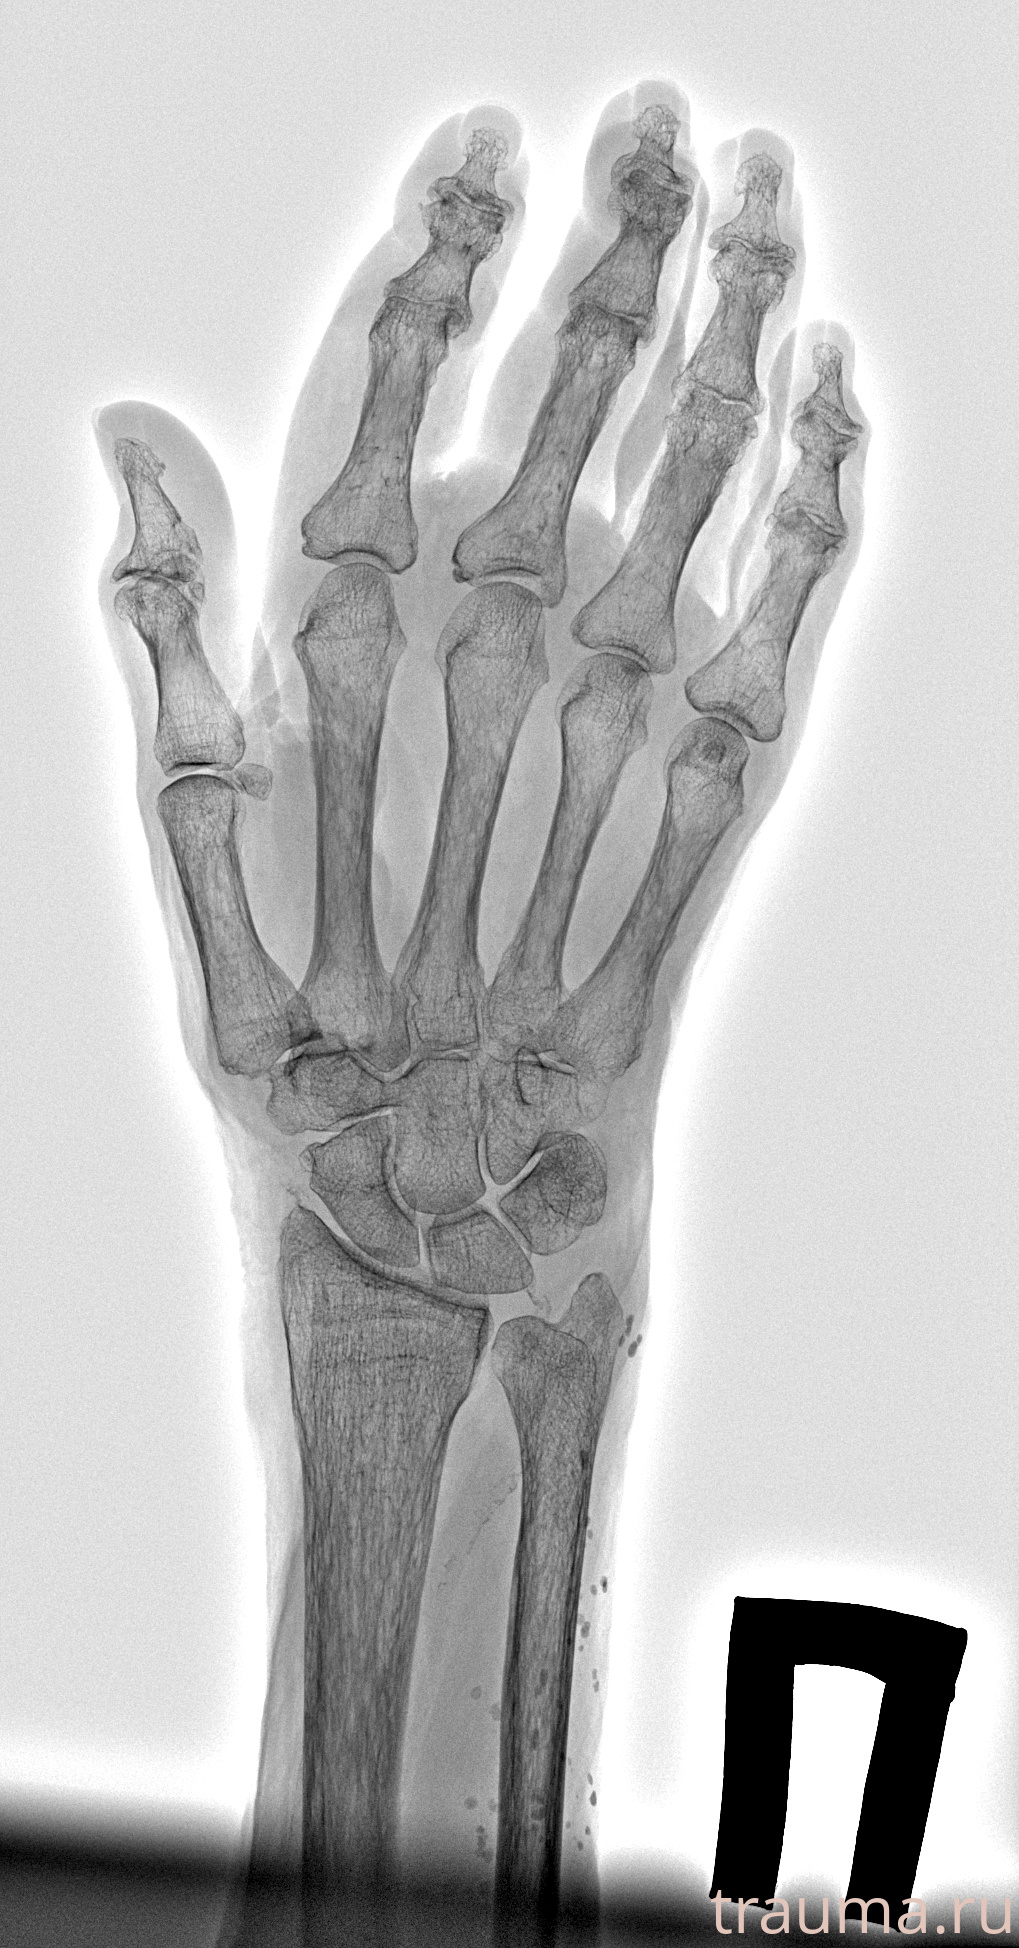

Рентгенограммы

Рентген на дому: по вашему адресу приезжает врач-рентгенолог, травматолог-ортопед с мобильным рентгеновским аппаратом, проводит диагностику травмы или заболевания, делает необходимые рентгенограммы, дает рекомендации по дальнейшему лечению. Получить качественные снимки в домашних условиях возможно благодаря уникальной методике, разработанной МосРентген Центром для института  Склифосовского